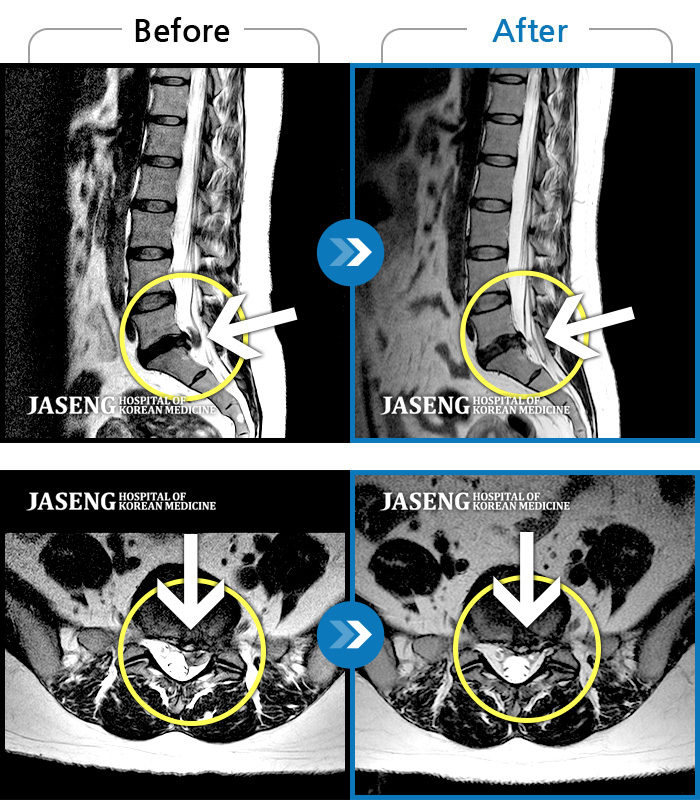

Before

After

환자에게 사전 동의를 받아 동일 조건에서 촬영되었습니다.

개인에 따라 치료 후 부작용이 발생할 수 있으니 의료진과 상담 후 치료를 진행하시기 바랍니다.

좌측요통 좌측하지방사통으로 타병원에서 8회 주사치료 후 호전 없어서 내원

양측 허리 통증, 우측 다리까지 이어지는 통증과 저림, 모든 자세에서 통증 심화